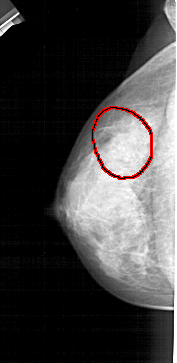

FILE: A_1446_1.LEFT_MLO.OVERLAY

TOTAL_ABNORMALITIES 1

ABNORMALITY 1

LESION_TYPE CALCIFICATION TYPE AMORPHOUS DISTRIBUTION SEGMENTAL

ASSESSMENT 2

SUBTLETY 3

PATHOLOGY BENIGN

TOTAL_OUTLINES 1

BOUNDARY